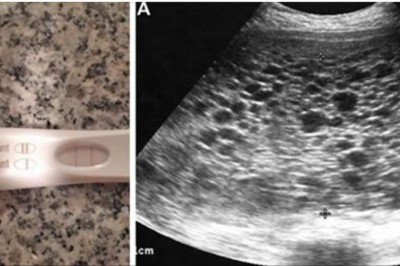

Widząc pozytywny test ciążowy bardzo się cieszy! Podczas USG lekarz zamiast dziecka dostrzega setki...

Pewna para była starała się o drugie dziecko i  gdy kobieta zrobiła test ciążowy Nie mogła powstrzymać radości. Okazało się, że wynik jest pozytywny. Mieli już jednego syna więc doskonale wiedzieli, że kolejne dziecko oznacza więcej radości, miłości i szc...